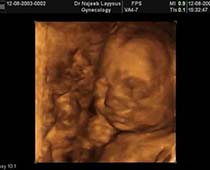

- Fetal Face Ultrasound Photos

- 3D Fetal Profile Ultrasound Scan Photos

- First Trimester Ultrasound Photos

- Multiple Pregnancy Ultrasound Photos

- The Clinical Advantages of 3D and 4D Ultrasound

- Definition and Features of Four Dimensional Ultrasound

- Uses of 4D Ultrasound scan

- The importance of 4D ultrasound imaging in pregnancy